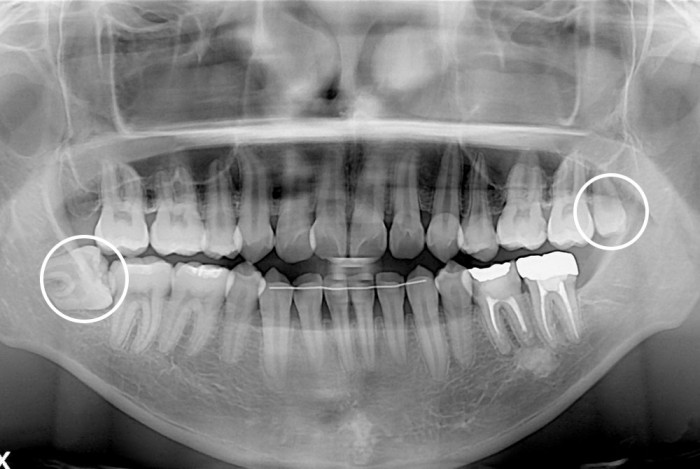

[사랑니] 사랑니

치료전 : 2020-02-13